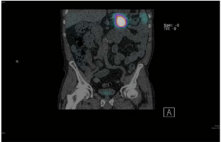

This mass was octreotide avid (Figure 4).

Figure 4 Positive Octreotide scan.